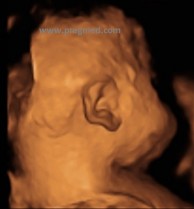

Fot. Obrazy twarzy płodu za pomocą techniki 3D/4D

Obraz twarzy płodu za pomocą techniki 3D 3D Mimika płodu w 3D